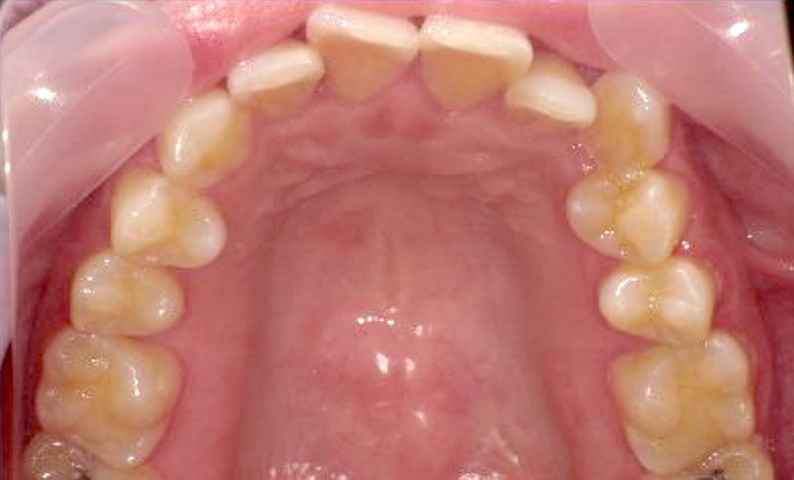

症例_002 上顎だけの部分矯正

治療期間:7ヶ月金額:30万円+税女性前歯のガタガタ上の前歯だけ

| Before | After |

|---|---|

|